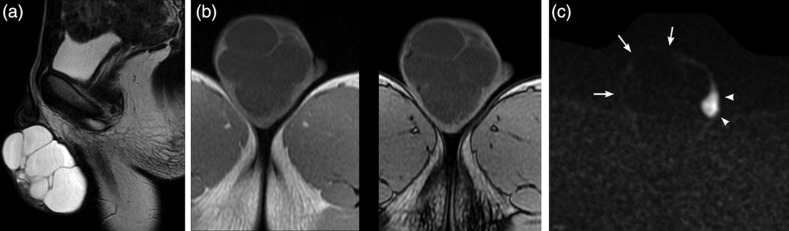

Lymphatic malformation/lymphangioma of the scrotum is rare. It is caused by lymphatic abnormalities and the most common sites are the neck and axilla. The scrotum is one of the most uncommon sites. We report the case of a 12-year-old boy with pathologically confirmed cystic lymphangioma/lymphatic malformation in the scrotum. The diagnosis was suspected from ultrasonography and magnetic resonance imaging. The most common cause of a cystic mass in the scrotum is scrotal hydrocele, but cystic lymphangioma/lymphatic malformation should be considered as a differential diagnosis for multicystic scrotal mass.